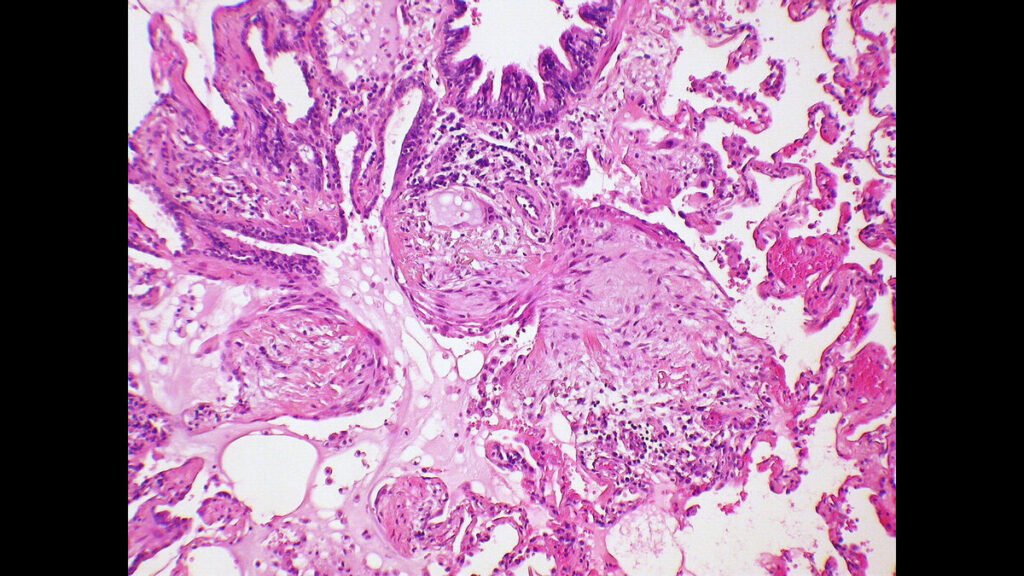

Cancer is a group of diseases characterized by uncontrolled cell growth that can invade surrounding tissues and spread to other parts of the body. It can affect virtually any organ or tissue and manifests differently depending on the type and stage. Early detection and timely treatment significantly improve outcomes, making awareness, regular screenings, and lifestyle choices crucial. Advances in medical research have led to targeted therapies, immunotherapy, and precision medicine, offering hope for improved survival and quality of life. Understanding cancer symptoms, risk factors, and prevention strategies is essential for informed health decisions.